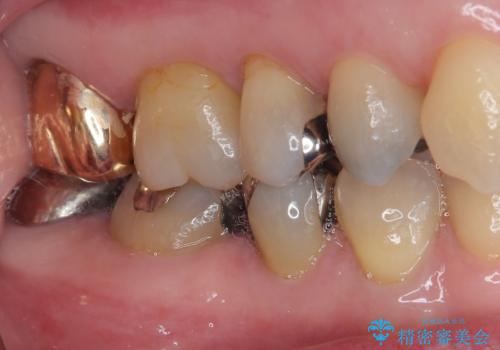

歯と歯茎の間に圧排糸と言われる糸を入れてシリコーン印象材にて精密な型どりをしました。

ハイブリッドインレーの装着時には、唾液の侵入を防ぐために、ラバーダム防湿を行いました。